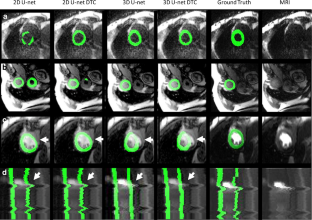

In this study, we compared different deep learning methodologies for CMR perfusion image segmentation. We evaluated the performance of several image segmentation methods using convolutional neural networks, such as the U-Net in 2D and 3D (2D plus time) implementations, with and without additional motion correction image processing step. We also present a modified U-Net architecture with a novel type of temporal pooling layer which results in improved performance.

The best DICE scores were 0.86 and 0.90 for LV myocardium and LV cavity, while the best Hausdorff distances were 2.3 and 2.1 pixels for LV myocardium and LV cavity using 5-fold cross-validation. The methods were corroborated in a second independent test set of 20 patients with similar performance (best DICE scores 0.84 for LV myocardium).

Our results showed that the LV myocardial segmentation of CMR perfusion images is best performed using a combination of motion correction and 3D convolutional networks which significantly outperformed all tested 2D approaches. Reliable frame-by-frame segmentation will facilitate new and improved quantification methods for CMR perfusion imaging.

• A deep learning approach in combination with motion correction, 3D (2D + time) methods, and a deep temporal connection module produced reliable segmentation results.

Fig. 1

Fig. 2

Fig. 3

Fig. 4

Fig. 5

Fig. 6